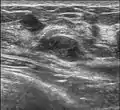

Histopathologic image of breast fibroadenoma. Core needle biopsy. H&E stain.

Since both fibroadenomas and breast lumps as a sign of breast cancer can appear similar, it is recommended to perform ultrasound analyses and possibly tissue sampling with subsequent histopathologic analysis in order to make a proper diagnosis. Unlike typical lumps from breast cancer, fibroadenomas are easy to move, with clearly defined edges.[1][2]

A fibroadenoma is usually diagnosed through clinical examination, ultrasound or mammography, and often a biopsy sample of the lump.[8] Suspicious findings on imaging may result in a person needing a biopsy in order to gain a definitive diagnosis. There are three types of biopsies: fine-needle aspiration, core-needle biopsy and surgical biopsy. The method of biopsy depends on the appearance, size and location of the breast mass.[18]